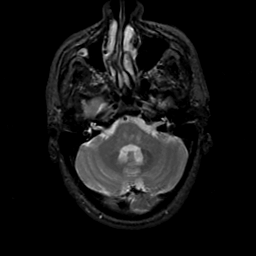

MR Study #19, August 25, 1991 -- Slice #11

[Home][Help][Clinical][Tour 1][Tour 2] Slice 11